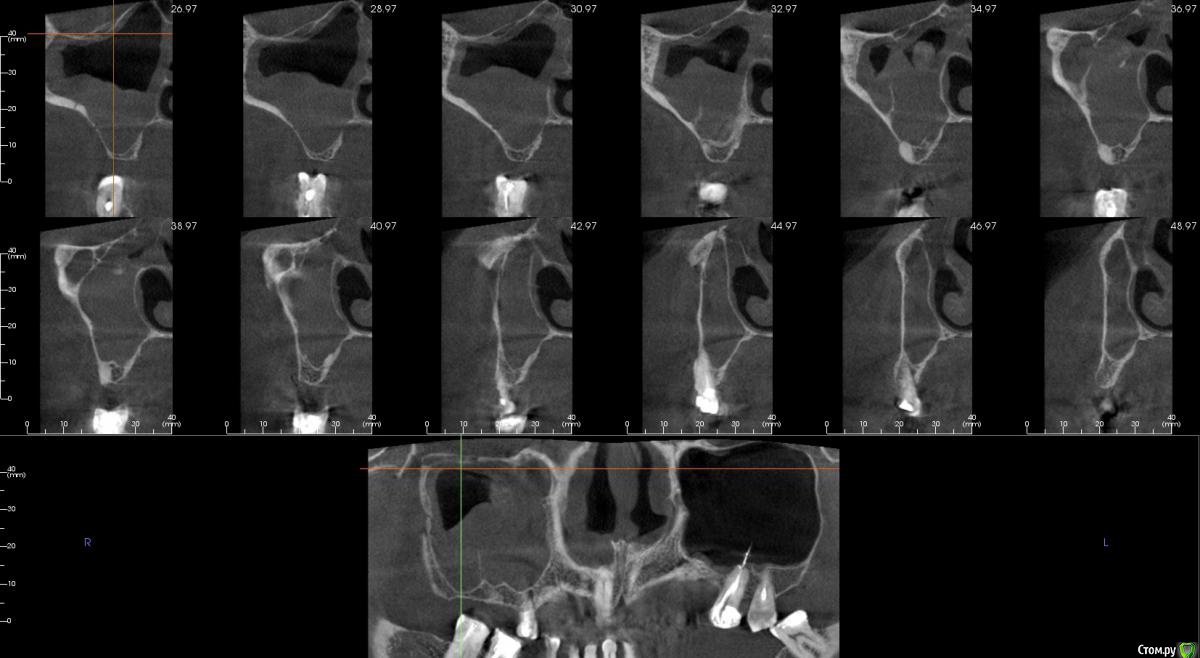

kamranchick Опубликовано 25 декабря, 2017 Автор Поделиться Опубликовано 25 декабря, 2017 (изменено) Чтобы не создавать новую тему...Пациента отправил на санацию ВЧП к лору, но вот такое дал заключение и сказал можно резать, ваше мнение? Изменено 25 декабря, 2017 пользователем kamranchick Ссылка на комментарий

егорджан Опубликовано 26 декабря, 2017 Поделиться Опубликовано 26 декабря, 2017 слева главное штырь торчит на сантим в пазуху и ничего Ссылка на комментарий

kamranchick Опубликовано 26 декабря, 2017 Автор Поделиться Опубликовано 26 декабря, 2017 слева главное штырь торчит на сантим в пазуху и ничегоштырь торчит 10 лет, полет нормальный, закапсулировался, у нас в стране имплантаты вгоняют так в пазуху и так же все хорошо() Ссылка на комментарий

Bier Опубликовано 26 декабря, 2017 Поделиться Опубликовано 26 декабря, 2017 ретенционку удали сам, через верхний доступ, этажем ниже делай синуслифт, если боишься, то в 2 этапа. Ссылка на комментарий

Irouil Опубликовано 27 декабря, 2017 Поделиться Опубликовано 27 декабря, 2017 Имхо не ретенционная, соустье вероятно перекрыто. Ссылка на комментарий